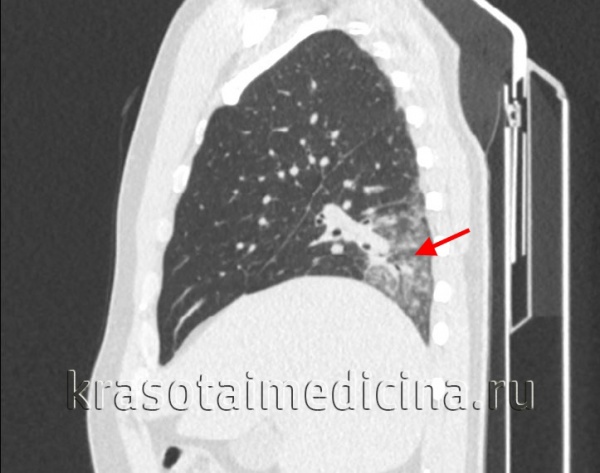

При подозрении на острую пневмонию назначается рентгенография легких в двух проекциях в динамике (на 7-10 день и 3-4 неделе). Рентгенологическим доказательством инфильтративных изменений при крупозной и крупноочаговой пневмонии является сегментарное или долевое гомогенное интенсивное затенение легочной ткани; при бронхопневмонии – неоднородное затенение части доли средней и малой интенсивности с захватом перибронхиальных и периваскулярных участков. В случае замедления рассасывания инфильтратов при острой пневмонии показана КТ легких.

КТ органов грудной клетки. Участок воспалительной инфильтрации (пневмония) в задних каудальных отделах нижней доли правого легкого

Бакпосев мокроты, крови, мочи позволяет установить возбудителя и его антибиотикочувствительность. Изменения ФВД рестриктивного типа (снижение ЖЕЛ, МВЛ, повышение МОД) характерны для обширной сливной очаговой и крупозной пневмонии. Бронхоскопию и бронхографию выполняют при затяжном течении острой пневмонии, что позволяет выявить наличие бронхоэктазов, полостей распада в легочной ткани. В рамках проводимой диагностики исключаются бронхит, рак легкого, туберкулез, инфаркт легкого, ателектатические бронхоэктазы.